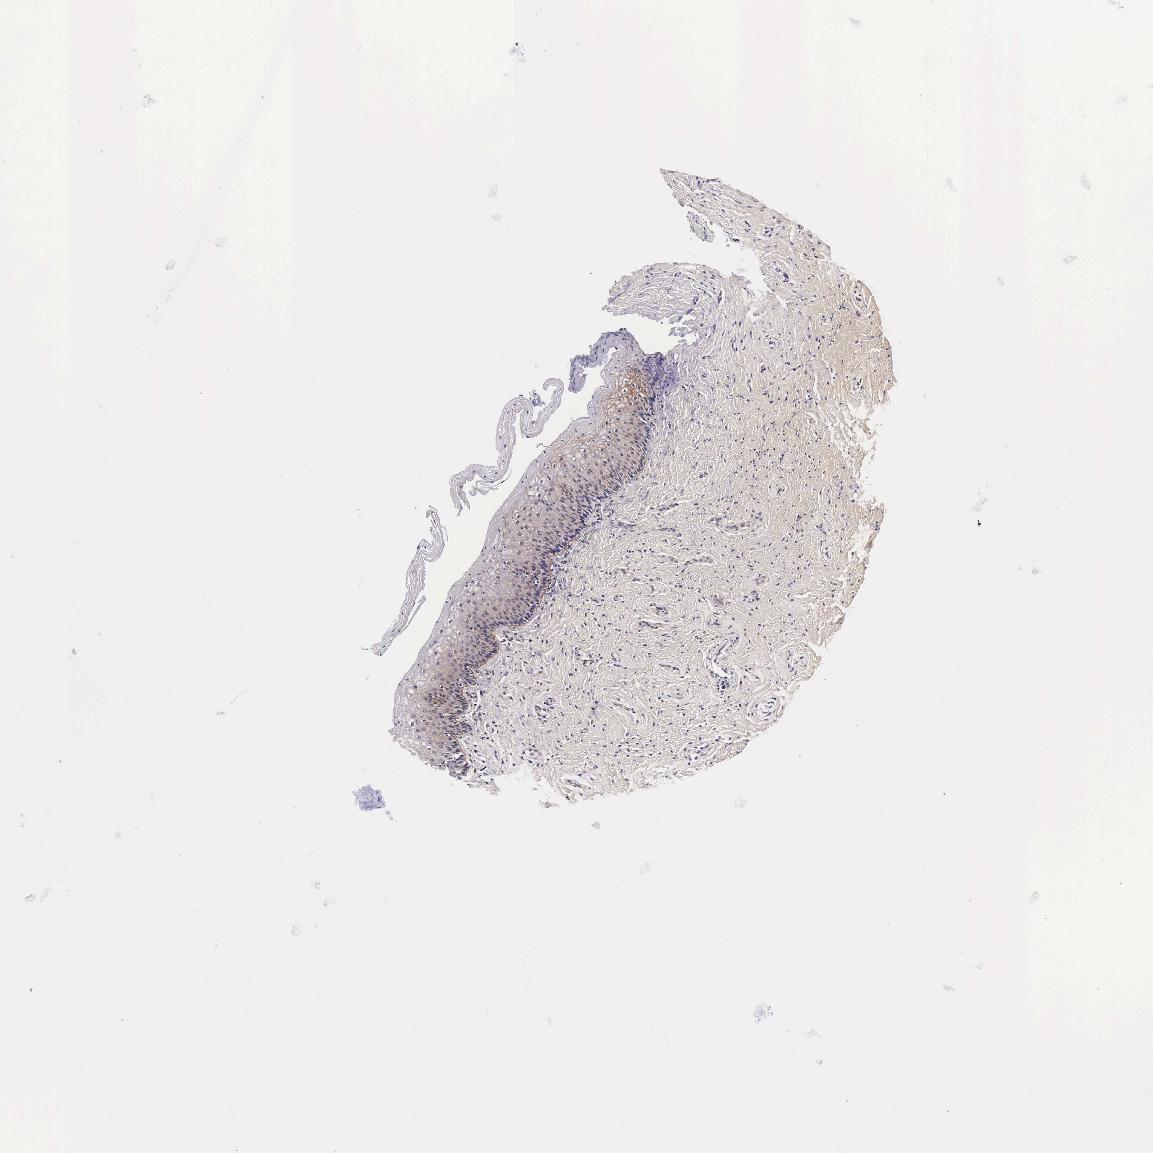

VAGINA - Antibody stainingi

Antibody staining in the annotated cell types in the current human tissue is reported as not detected, low, medium, or high, based on conventional immunohistochemistry profiling in selected tissues. This score is based on the combination of the staining intensity and fraction of stained cells.

Each image is clickable and will lead to virtual microscopy that enables deeper exploration of all samples and also displays staining intensity scores, fraction scores and subcellular localization as well as patient and tissue information for each sample.

Antibody HPA000647

Squamous epithelial cells Not detected